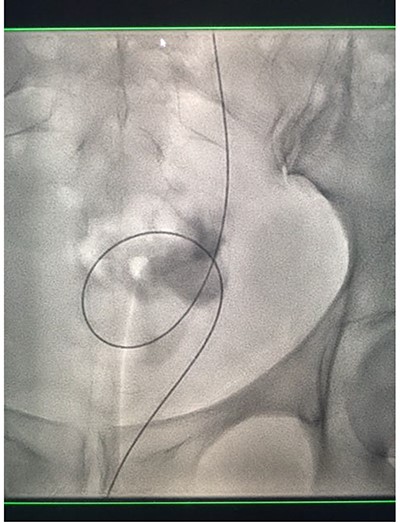

Under conscious sedation, using the previously inserted right percutaneous nephrostomy, antegrade access was achieved into the intrarenal collecting system and then into the proximal ureter. An 8 Fr × 11-cm access sheath was introduced. A guidewire was advanced antegradely through the site of ureteric transection and coiled in a position adjacent to the position of the guidewire that had been inserted retrogradely. A Gooseneck snare catheter was then passed over the guidewire and the snare was inserted (Figs 4 and 5). Under fluoroscopic guidance, the retrograde wire was retrieved and brought externally via the nephrostomy site, achieving through-and-through wire access (Figs 6 and 7).

Fluoroscopic images showing the antegrade Amplatz gooseneck snare catheter attempting to grasp the retrograde wire.